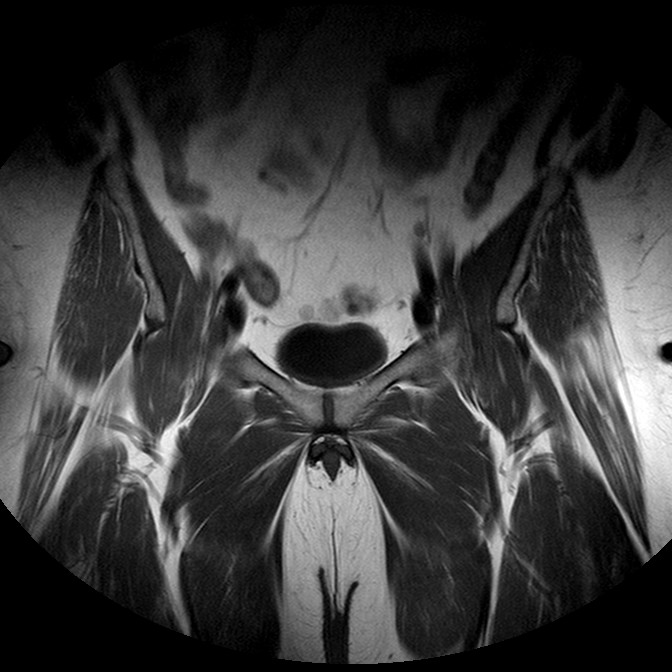

Esami: RMN BACINO

T1w TSE

Evidenti e simmetriche alterazioni osteofitosiche in regione coxo femorale con riduzione delle rime articolari. Degenerazione completa del cercine glenoideo. Non attuali segni di versamento articolare. Non segni di edema osseo che escludono attuale algodistrofia od osteonecrosi. Lieve e simmetrica riduzione del trofismo della muscolatura glutea.